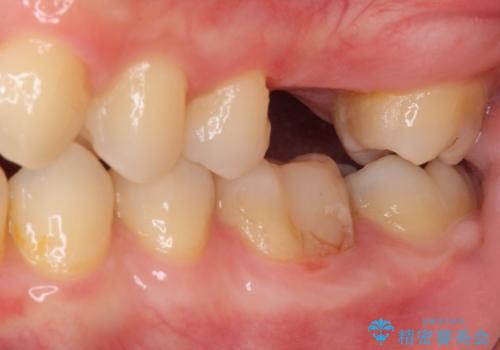

- 前歯のクロスバイトと、大学生のころから放置している虫歯を気にして来院された患者様です。

マウスピースでの矯正治療を希望されていましたが、前歯のクロスバイトは不十分な仕上がりや歯髄壊死などのリスクが高くなるため、術前にワイヤーで大まかに整えてからインビザラインにて矯正治療を行うこととしました。